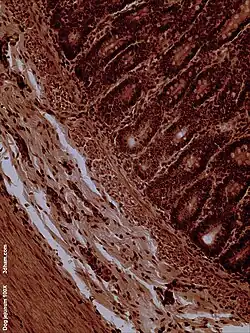

Dog jejunum (magnified 100-fold)

Function